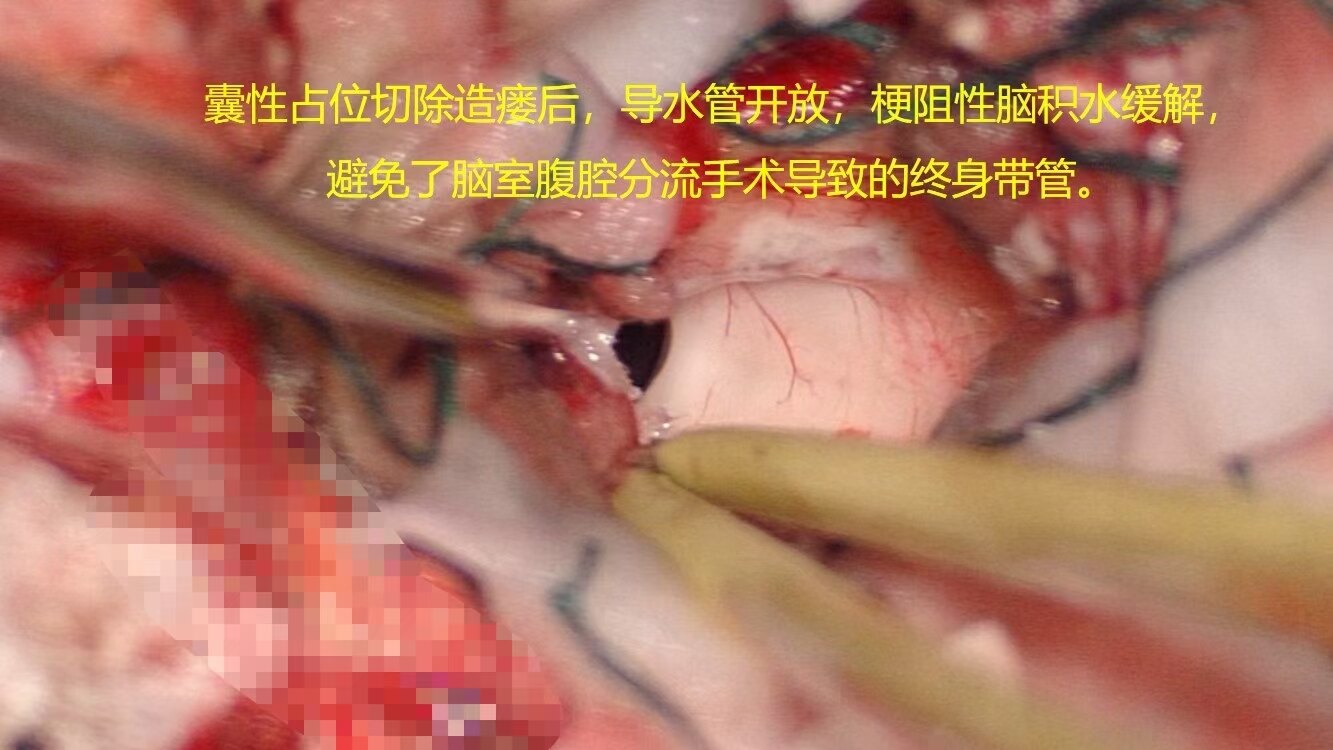

后颅窝占位引起梗阻性脑积水,术前已经出现视力模糊,脑室ommaya测压大于50cm水柱,临时外引流缓解颅压后患儿视力有恢复,后急诊行后颅窝占位切除,术中切除囊性占位、打通中脑导水管、解除脑干压迫,术后脑积水缓解满意,患儿状态良好。